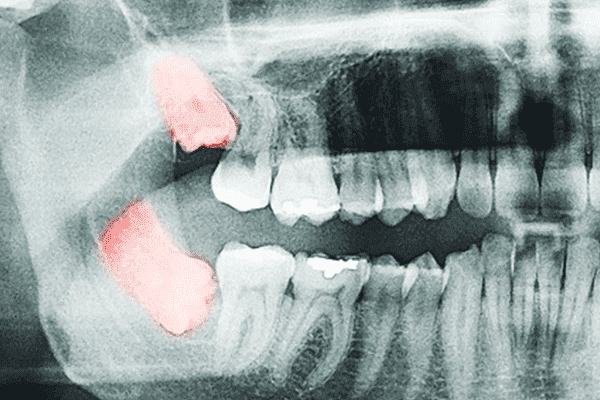

しかし、従来の2次元のレントゲンでは、平面のレントゲン画像で診断するため、難しい症例の診断が確実ではありませんでした。

当院では、最新のCTレントゲンを導入することにより、顎の状態を的確に把握し、抜くべきか抜かないべきか、安全な治療のためにはどのような処置をすべきかなどの診断をすることが可能になりました。

より安全で、確実な診断・治療を行うためにはCTはもはや欠かせない機器となりました。

CTレントゲン撮影による診断と、患者様からのヒアリングを丁寧に行うことで、その方へのベストな処置方法を選択します。

また、歯肉に埋まってしまっている親知らず(埋伏歯)の場合や、難症例の場合にはCTの撮影も行います。

顎の状態を確実に把握できるため、安全性の高い治療が可能です。

- 歯の根元が顎の神経に近くないかどうかを確認します(安全に処置をするために重要)

もし、骨の中で 神経や血管が親知らずと近い状態であれば安全、万全を期するためにCT撮影を行うことができます。